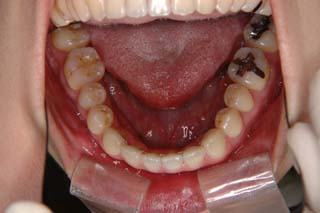

外科症例(アゴの輪郭でお悩みの方) 下顎前突

装置撤去です。動的処置は2年弱でしたので、通常のマルチブラケット治療とそれほど治療期間は変わりません。しかしながら、わずかな正中のズレが残ってしまいました。大きくは改善したのですが、左右のズレというものは、比較的、後戻りが現れやすい問題です。筋肉の影響によるものや、咬合平面の傾斜が左右的に水平でない事などが関係しているような気がします。今後は保定治療に移行し、数年にわたって咬合の安定状態を管理していきます。